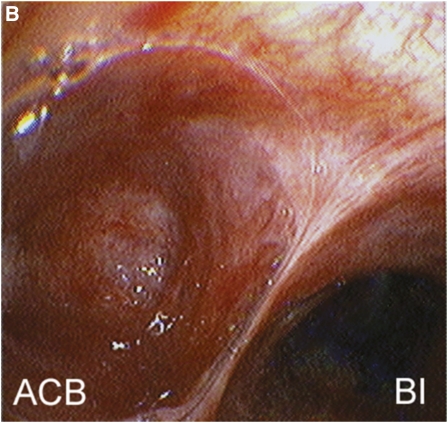

A 57-year-old man underwent high-resolution computed tomography (HRCT) scanning and bronchoscopy as part of an evaluation for dyspnea and exercise intolerance. Physical examination was without abnormalities. Incidental note was made of an air-filled structure (black arrow) medial to the bronchus intermedius (BI) on HRCT (Figure 1). Bronchoscopy revealed normal airways, except for an accessory (cardiac) bronchus (ACB) arising from the BI (Figure 2).

Figure 2.

ACB occur in up to 0.5% of the general population and usually end as a blind pouch. They may also be associated with small amounts of pulmonary parenchyma. ACB are almost always an incidental finding, although they may be a reservoir of infectious material, source of hemoptysis, or origin of malignancy. The most common location of ACB is the inferomedial wall of the right mainstem bronchus, but can be found arising from the BI as seen in this patient.